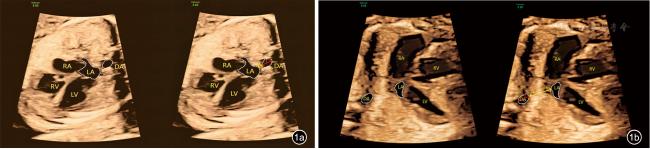

APVS组20例(图2),孕妇平均年龄(27.5±3.6)岁,平均诊断GA(24.9±2.1)周。对照组261例,孕妇平均年龄(30.6±3.6)岁,行胎儿超声心动图检查的GA范围16~37+1周,平均GA(26.9±4.4)周。

图2 肺动脉瓣缺如综合征胎儿四腔心切面及右心室流出道-肺动脉分支切面超声图像。图a为四腔心切面显示左右心比例不对称,右心明显增大,心轴左偏;图b红框标记为肺动脉瓣环处,未见明显瓣叶结构回声。肺动脉主干及左右分支显著扩张,呈“鲸鱼尾”征;图c,d为彩色多普勒图像,显示肺动脉瓣环处往返于右心室与肺动脉之间的高速“穿梭”样血流信号,其中图c为舒张期,可见由明显扩张的肺动脉主干及分支反流进入右心室的红色血流信号;图d为舒张期,可见右心血流经过肺动脉瓣环冲击肺动脉及其分支的蓝色血流信号

注:LA为左心房;LV为左心室;RA为右心房;RV为右心室;LPA为左肺动脉;RPA为右肺动脉;DA为降主动脉